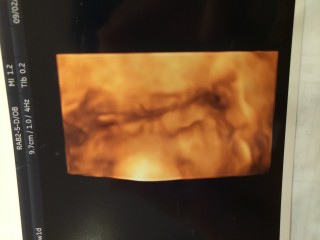

性別は女の子で確定。初めての4Dでしたが、お顔を見せてもらえました♡ 鼻筋の通った美人さんだと義両親にも言われ、生まれてくるのが楽しみです(^^)

体重は765g、順調に育ってるそうです。4Dエコーでは可愛い寝顔を見せてくれました。 18週の時の4Dエコーと比べて赤ちゃんらしい顔つきになっていてビックリしました。元気にすくすく育ってね。